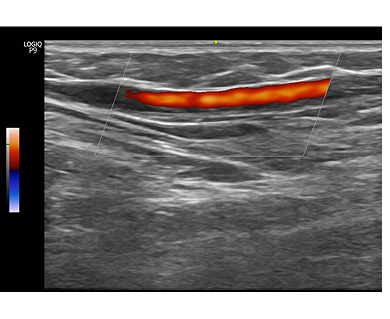

하지정맥류 진단은 혈액의 역류 진단은 육안으로는 다 알 수 없습니다.

혈관 초음파를 통해 발병 부위를 면밀히 관찰해야 합니다.

| 정상 하지정맥 | 역류가 일어난 하지정맥 | |

도플러 초음파 검사라는 혈관 초음파 검사를 통해 고장난 판막의 위치와 역류 시간을 정확하게 파악할수 있는 검사입니다. |